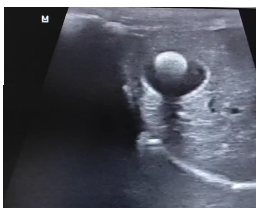

Метод выбора – УЗИ (рис.1)

(чувствительность и специфичность 95%).

Рис.1. Округлы гиперэхогенный холелит в полости желчного пузыря с чёткой акустической тенью.